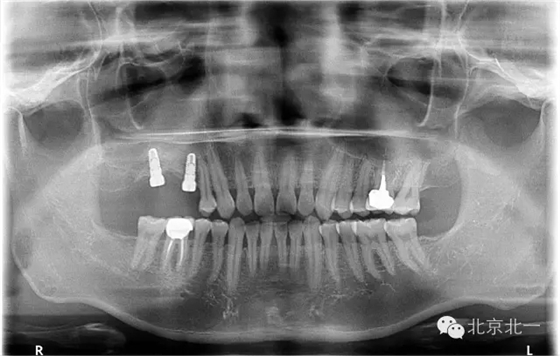

圖二:手術前全景片

圖二十三:種植后當天全景片。